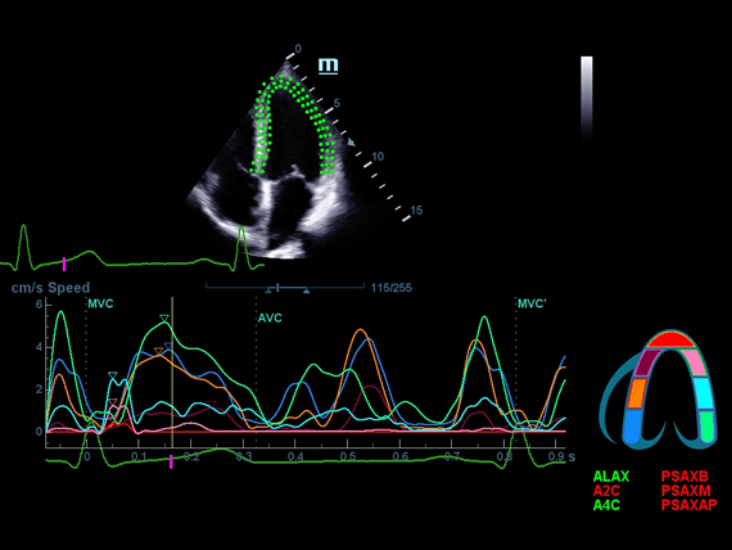

Klinische Bilder